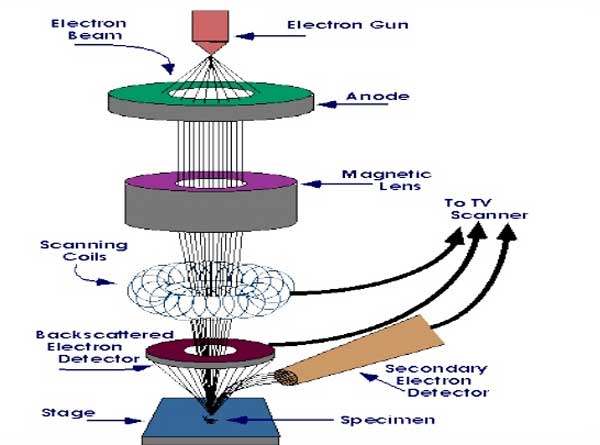

এখন যে ভাবে কাজ চলে, সেই এক্স-রে ক্রিস্টালোগ্র্যাফি

এক্স-রে ক্রিস্টালোগ্র্যাফিতে যে ভাবে দেখা হয় প্রোটিন কেলাস

এক্স-রে ক্রিস্টালোগ্র্যাফিতে যে ভাবে দেখা হয় প্রোটিন কেলাস

এক, ‘ক্রায়ো-ইএম’ পদ্ধতিতে কাজটা করতে দ্রবণ বা সলিউশনের প্রয়োজন হয়। মানে, একটা তরল অবস্থা। যাতে একই সঙ্গে অনেকগুলি প্রোটিন থাকে। তবে তা স্বাভাবিক তাপমাত্রার তরল অবস্থা নয়। ‘ফ্রোজেন লিক্যুইড’ অবস্থা। মানে, হিমাঙ্ক বা ‘ফ্রিজিং পয়েন্ট’ বা শূন্য ডিগ্রি সেন্টিগ্রেডের নীচে থাকা অবস্থা। যা আদতে কঠিন। কিন্তু কেলাস বা ‘ক্রিস্টাল’ নয়। ফলে, একই সঙ্গে অনেকগুলি প্রোটিনের গঠন-কাঠামো আর তাদের চলাচলকে দেখা যায় ‘ক্রায়ো-ইএম’ পদ্ধতিতে। এটা এক্স-রে ক্রিস্টালোগ্র্যাফিতে সম্ভব নয়। কারণ, ওই পদ্ধতিতে প্রোটিন শুধুই কোনও কেলাস (ক্রিস্টাল, মানে, কঠিন পদার্থ) অবস্থায় থাকলে, তবেই তাকে দেখা যায়। আর যেহেতু ওই পদ্ধতিতে কোনও দ্রবণ থাকে না, তাই একই সঙ্গে একাধিক প্রোটিন অণুর গঠন-কাঠামো দেখার সুযোগ থাকে না এক্স-রে ক্রিস্টালোগ্র্যাফিতে।

এখন আরও একটি পদ্ধতির ব্যবহার হয়। তার নাম- ‘নিউক্লিয়ার ম্যাগনেটিক রেজোন্যান্স’ বা ‘এনএমআর’

দুই, যে প্রোটিন অণু বা বিভিন্ন প্রোটিনের অণুগুলির গঠন-কাঠামো দেখা হয় এই ‘ক্রায়ো-ইএম’ পদ্ধতিতে, তা খুব সামান্য পরিমাণে থাকলেই কাজ হয়ে যায়। এক্স-রে ক্রিস্টালোগ্র্যাফিতে কিন্তু কোনও প্রোটিন কেলাসকে ভাল ভাবে দেখতে গেলে তা বেশি পরিমাণে না থাকলে হয় না।

তিন, দশায় দশায় কোনও প্রোটিন অণু বা অণুগুলির ‘রূপবদল’ হয়। এটাকে বলে ‘ফেজ ট্রান্সফর্মেশন’। তাদের অবস্থার পরিবর্তন। সেই পরিবর্তনের কিছু গুরুত্বপূর্ণ সংকেত থাকে, বার্তা থাকে। যাদের বলা হয় ‘ফেজ ইনফর্মেশন’। এই ‘ফেজ ইনফর্মেশন’-এর অনেকটাই এক্স-রে ক্রিস্টালোগ্র্যাফিতে হারিয়ে যায়। যা ‘ক্রায়ো-ইএম’-এ কোনও দিনই হবে না।

চার, সে জন্যই ‘ক্রায়ো-ইএম’ পদ্ধতির ছবির রেজোলিউশন অত ভাল, অত নিখুঁত, অত সূক্ষ্ণ হয়।

পাঁচ, বহু প্রোটিনকে কেলাস অবস্থায় পাওয়া যায় না। তাই ওই সব প্রোটিনের এক্স-রে ক্রিস্টালোগ্র্যাফি করাও যায় না।